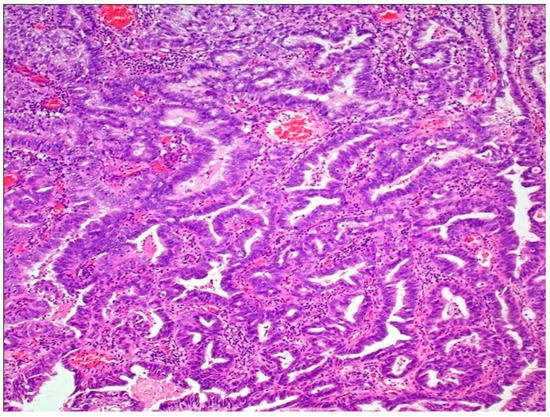

Figure 5.

Adenocarcinoma of bladder.